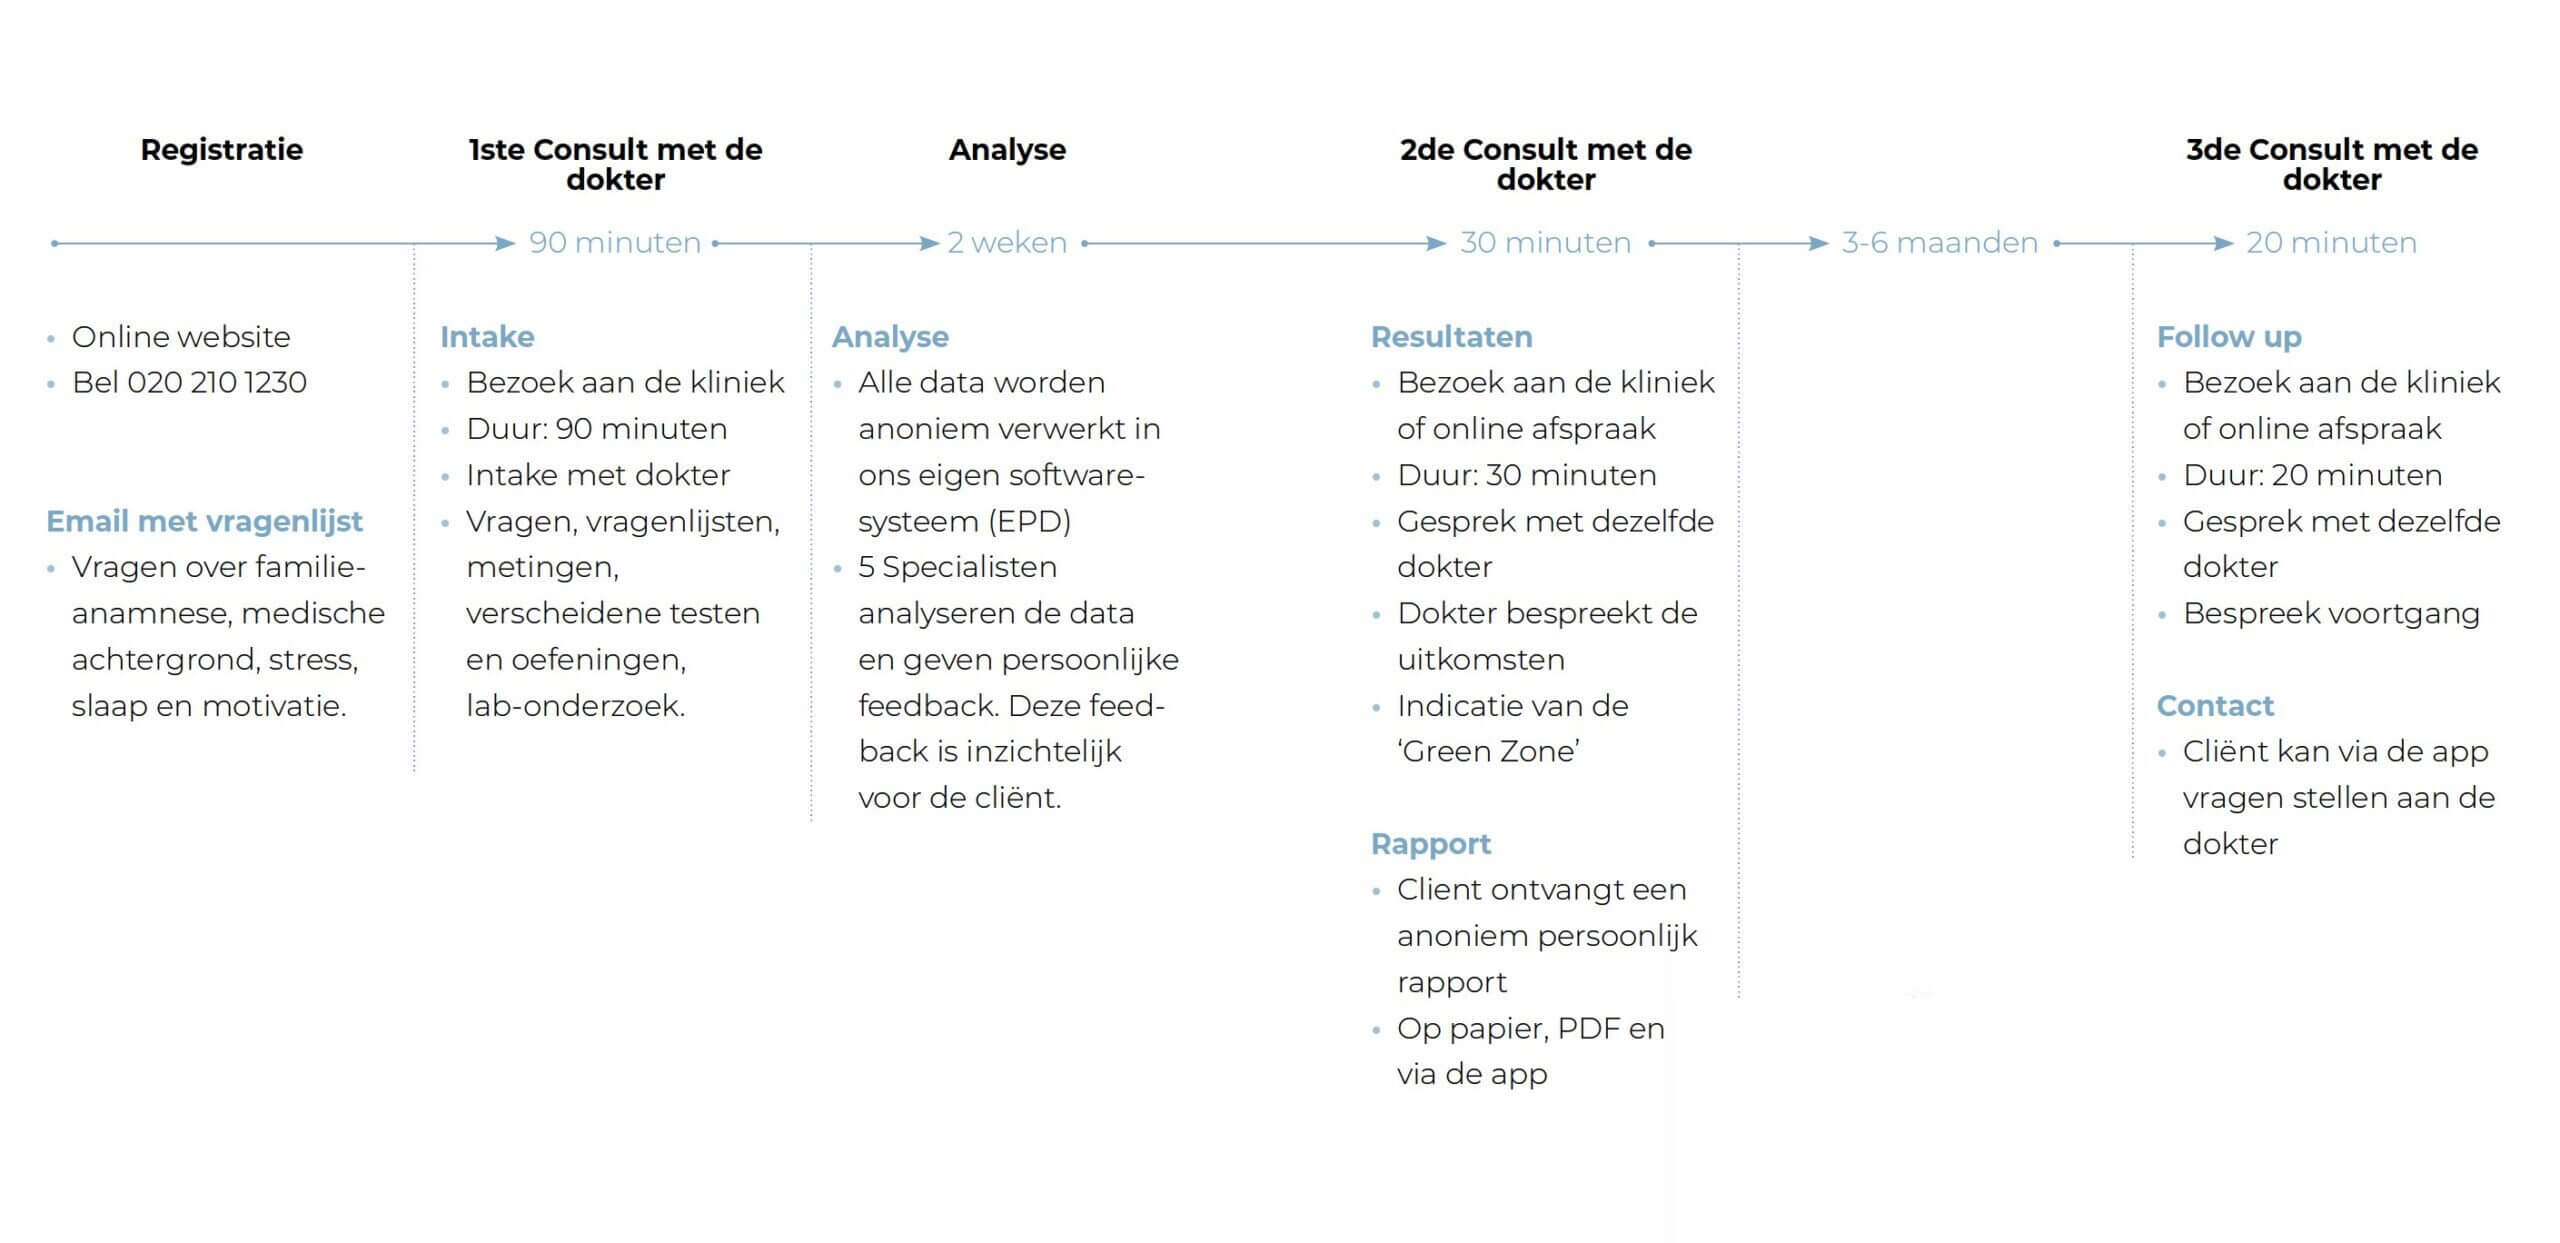

Tijdlijn van de Health Check

Je krijgt een totaalbeeld

Om zo het beste advies te kunnen krijgen

Je krijgt inzicht in heel veel biomarkers

Samengesteld in een duidelijk rapport

We nemen de tijd

Ieder mens is anders. Wij hebben de tijd om echt te luisteren,

steeds door dezelfde arts en team van specialisten

We nemen de tijd voor het intake gesprek. Al jouw vragen en zorgen komen aan bod.

Na twee weken volgen de resultaten. Dit gesprek is persoonlijk en we hebben de tijd voor alle resultaten.

Met de Easy Health Steps ga je vervolgens zelf aan de slag. Wil je begeleiding? Dat kan ook!